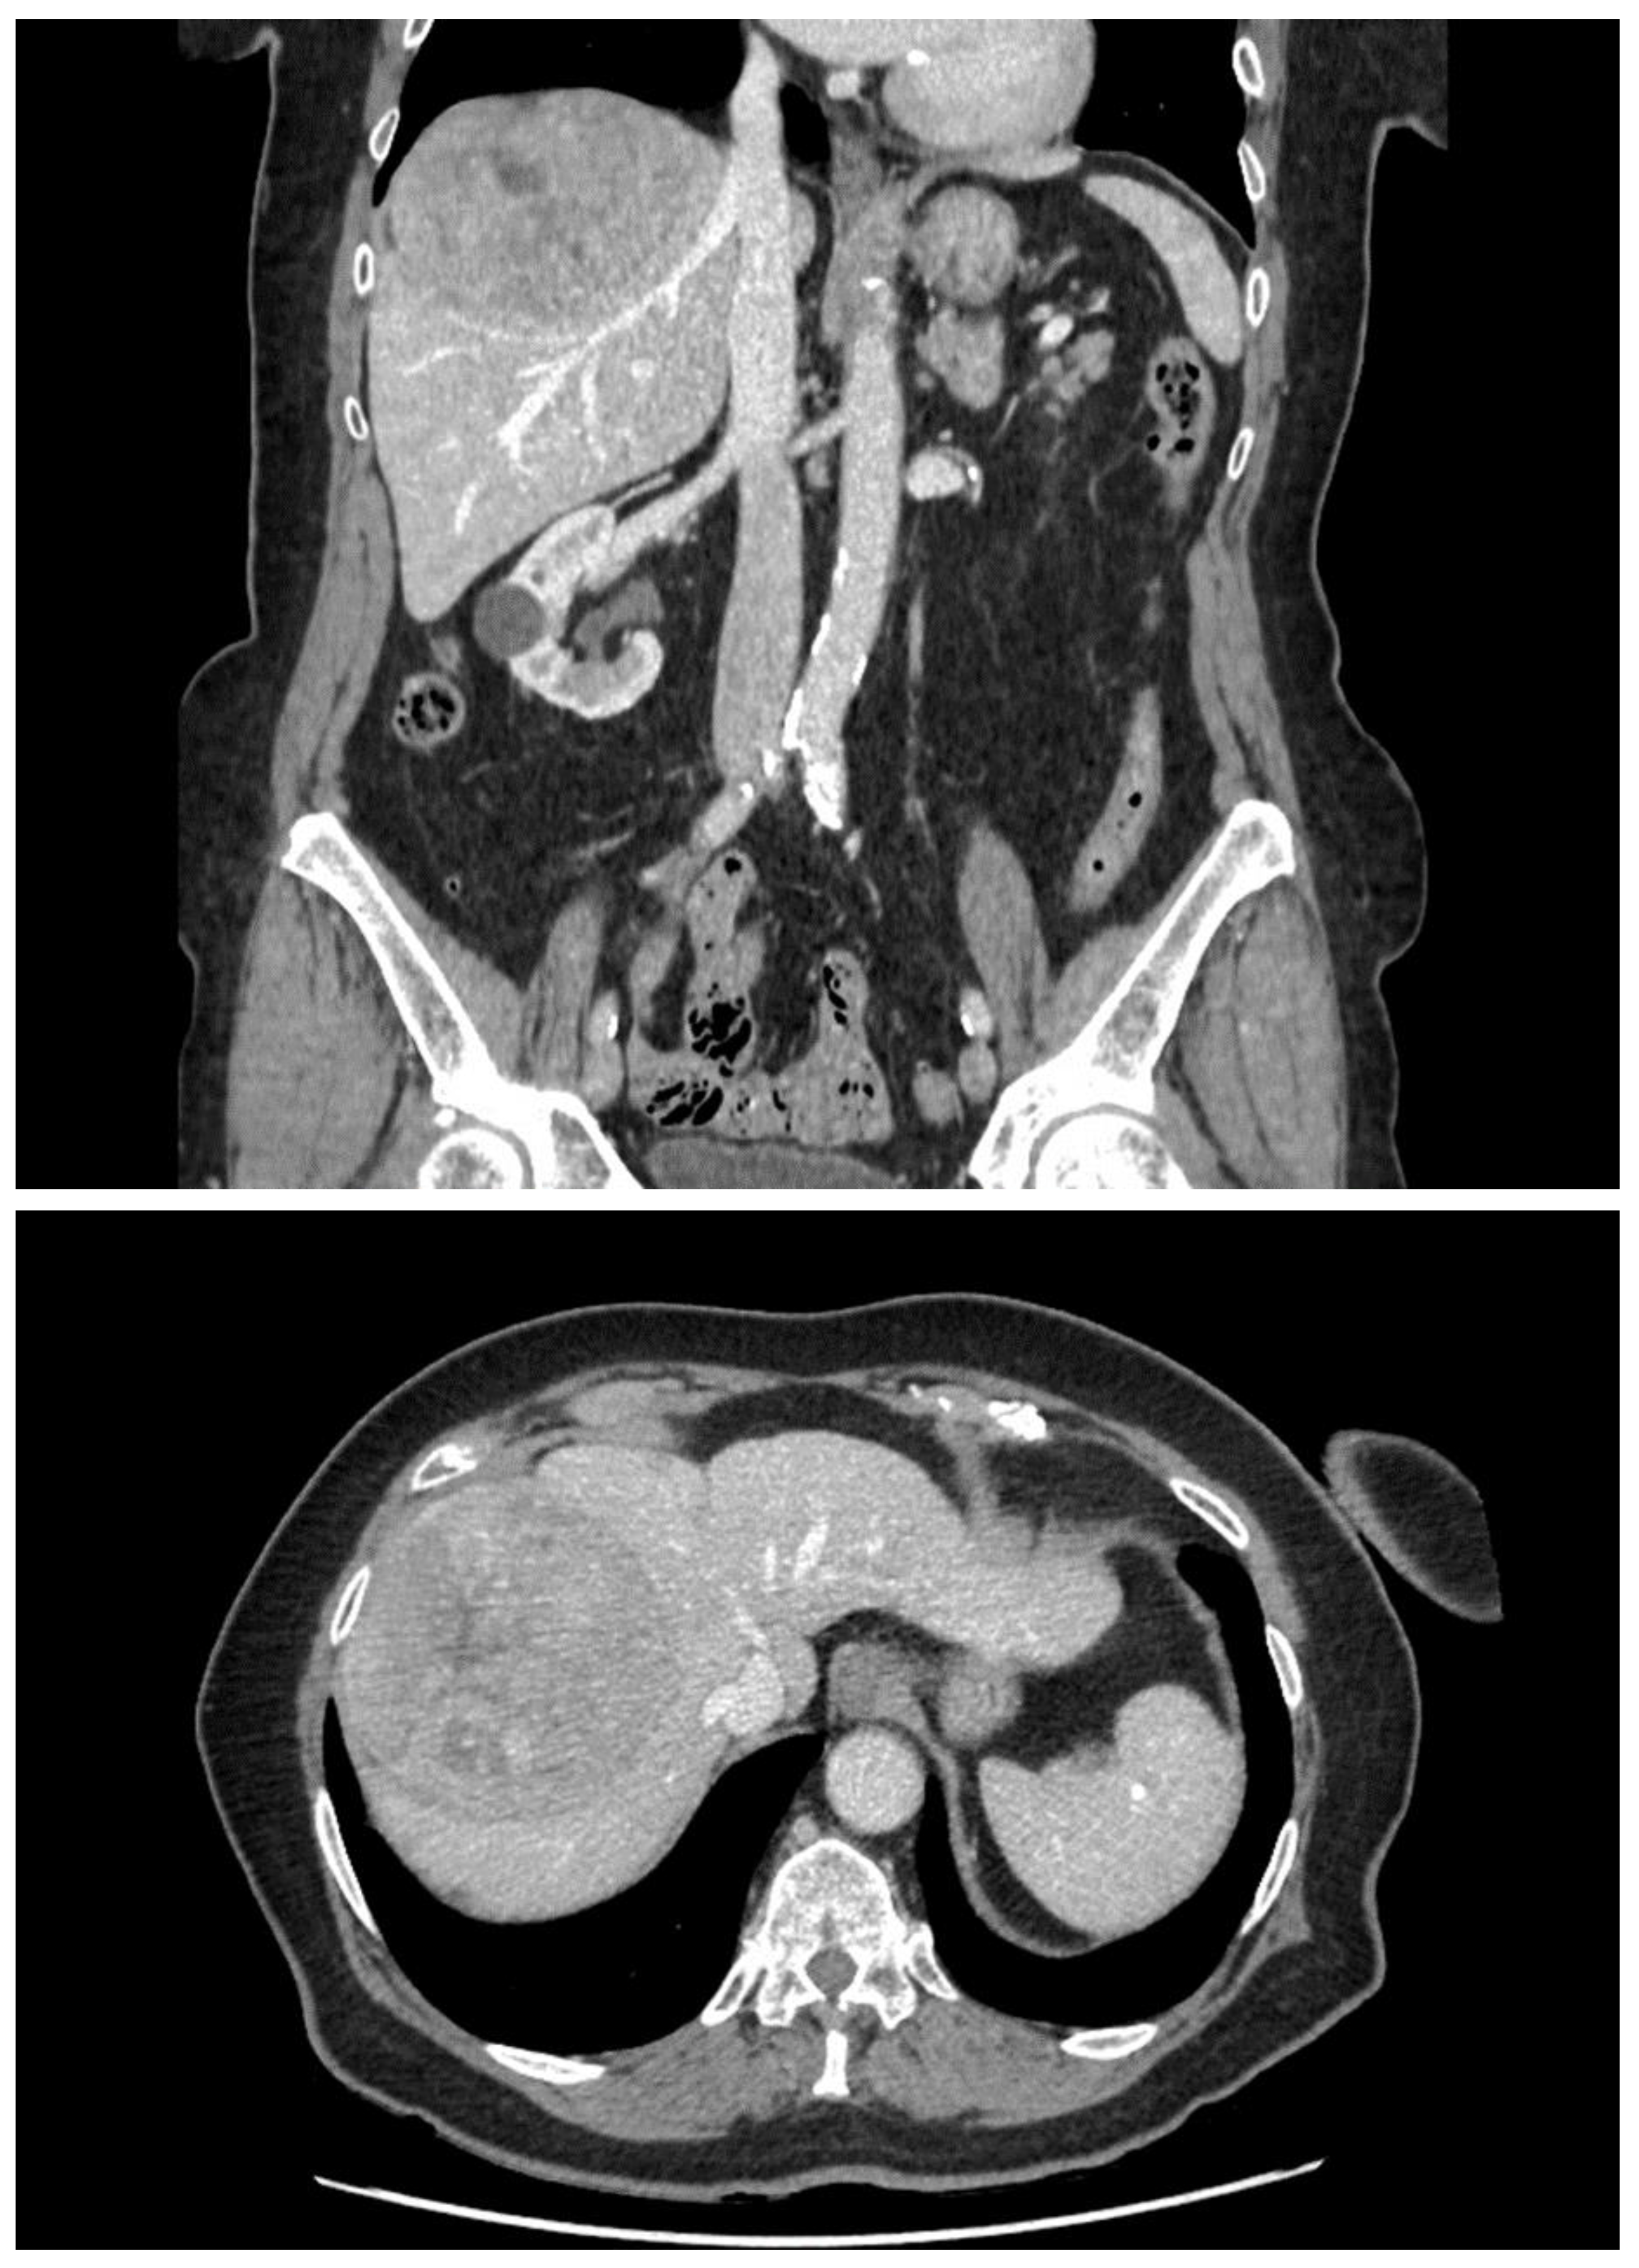

2. Case Report